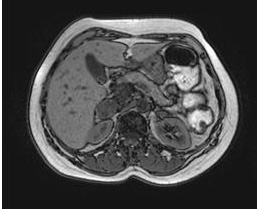

Wenn die Bestimmung der Plasma-Metanephrine wiederholt ein positives Ergebnis bringt, muss eine weiterführende Lokalisationsdiagnostik durchgeführt werden. Dies geschieht mittels bildgebender Verfahren wie der Sonografie und Computertomografie oder der Magnetresonanztomografie. Die nuklearmedizinische Methode der MIBG-Szintigrafie (Metaiodobenzylguanidin), bei der es sich um eine Substanz handelt, die sich in den betroffenen chromaffinen Zellen des Phäochromozytoms anreichert, dient zur Lokalisation von extraadrenal (= außerhalb der Nebennieren) gelegenen Tumoren. Für die Detektion von Metastasen stellt die sensitivste Methode die 6-[18F]-Fluorodopamin-PET (= Positronenemissionstomografie) dar. Die neueste und zuverlässigste nuklearmedizinische Methode zur Phäochromzytomdiagnostik ist das so genannte DOPA-PET.

| Bildgebende Verfahren beim Phäochromozytom | |